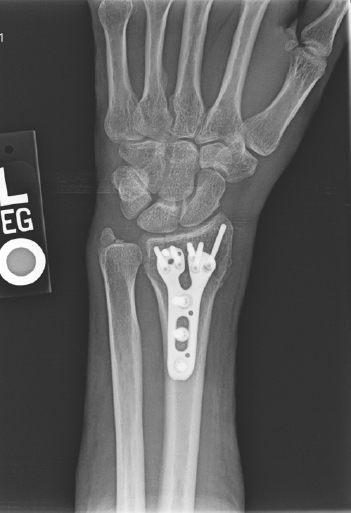

X-rays will be used to confirm the diagnosis. Fortunately, many of these fractures can be treated without surgery. Sometimes, the best thing is to push the fracture back into a better position and then hold it there with a cast. However, there are occasions where surgery is the best option. Surgery allows for the bones to be held in a better position more securely. With surgery, the bones can be held in place with pins, plates, and screws, and sometimes a combination of all of these. No matter the treatment, these fractures usually require at least 6 weeks to heal before it is ok to begin using the hand and wrist without restriction, but it often takes months before the pain and the stiffness fully resolve.

60-year-old female without other medical problems fell and landed primarily on her left hand and wrist. She had immediate pain and deformity at the wrist. She went to the emergency room where x-rays were performed showing her injury – a distal radius fracture. An attempt was made at improving the fracture position by the emergency room doctors and she was splinted. She was then referred to my clinic. She was seen soon afterwards. It was noted on new x-rays that the broken bone was in a less than ideal position. After a thorough discussion of the patient’s goals and concerns, surgery was felt to be the best option for her. Surgery was performed one week after her initial injury under general anesthesia. She was allowed to begin moving her wrist after her first post-operative visit 10 days after surgery and begin full weight bearing on the hand and wrist just under 6 weeks after surgery. She now has full function.